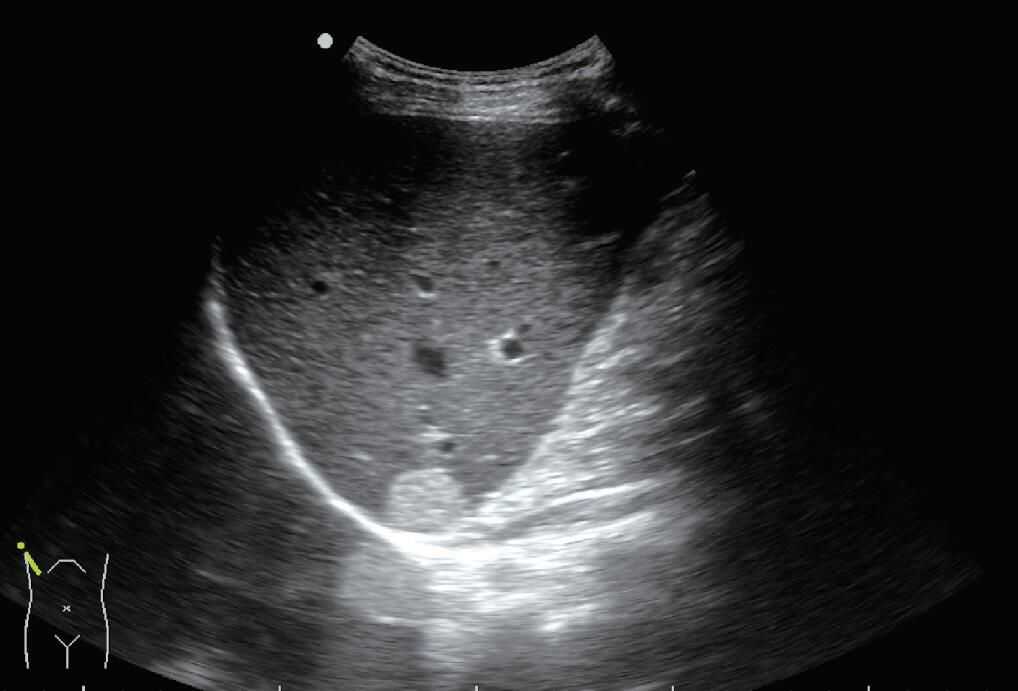

(8)侧边声影和“回声失落”:超声在通过囊肿边缘或肾上、下极侧边时,可以由于折射而产生边缘声影或侧边“回声失落”(全反射)。侧边声影也见于细小血管和主胰管的横断面,呈小“=”征,而非小圆形(图13)。

图13如箭头所示,肝内胆管横断面呈现“=”征